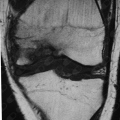

- Cirurgia do Joelho

Fotos

Artroplastia Total Primaria Do Joelho

Artroscopia

Artroscopia Cirurgica Do Joelho

Reconstrução ligamentar intra-articular do joelho (Ligamentoplastia)

- Cirurgia do Joelho